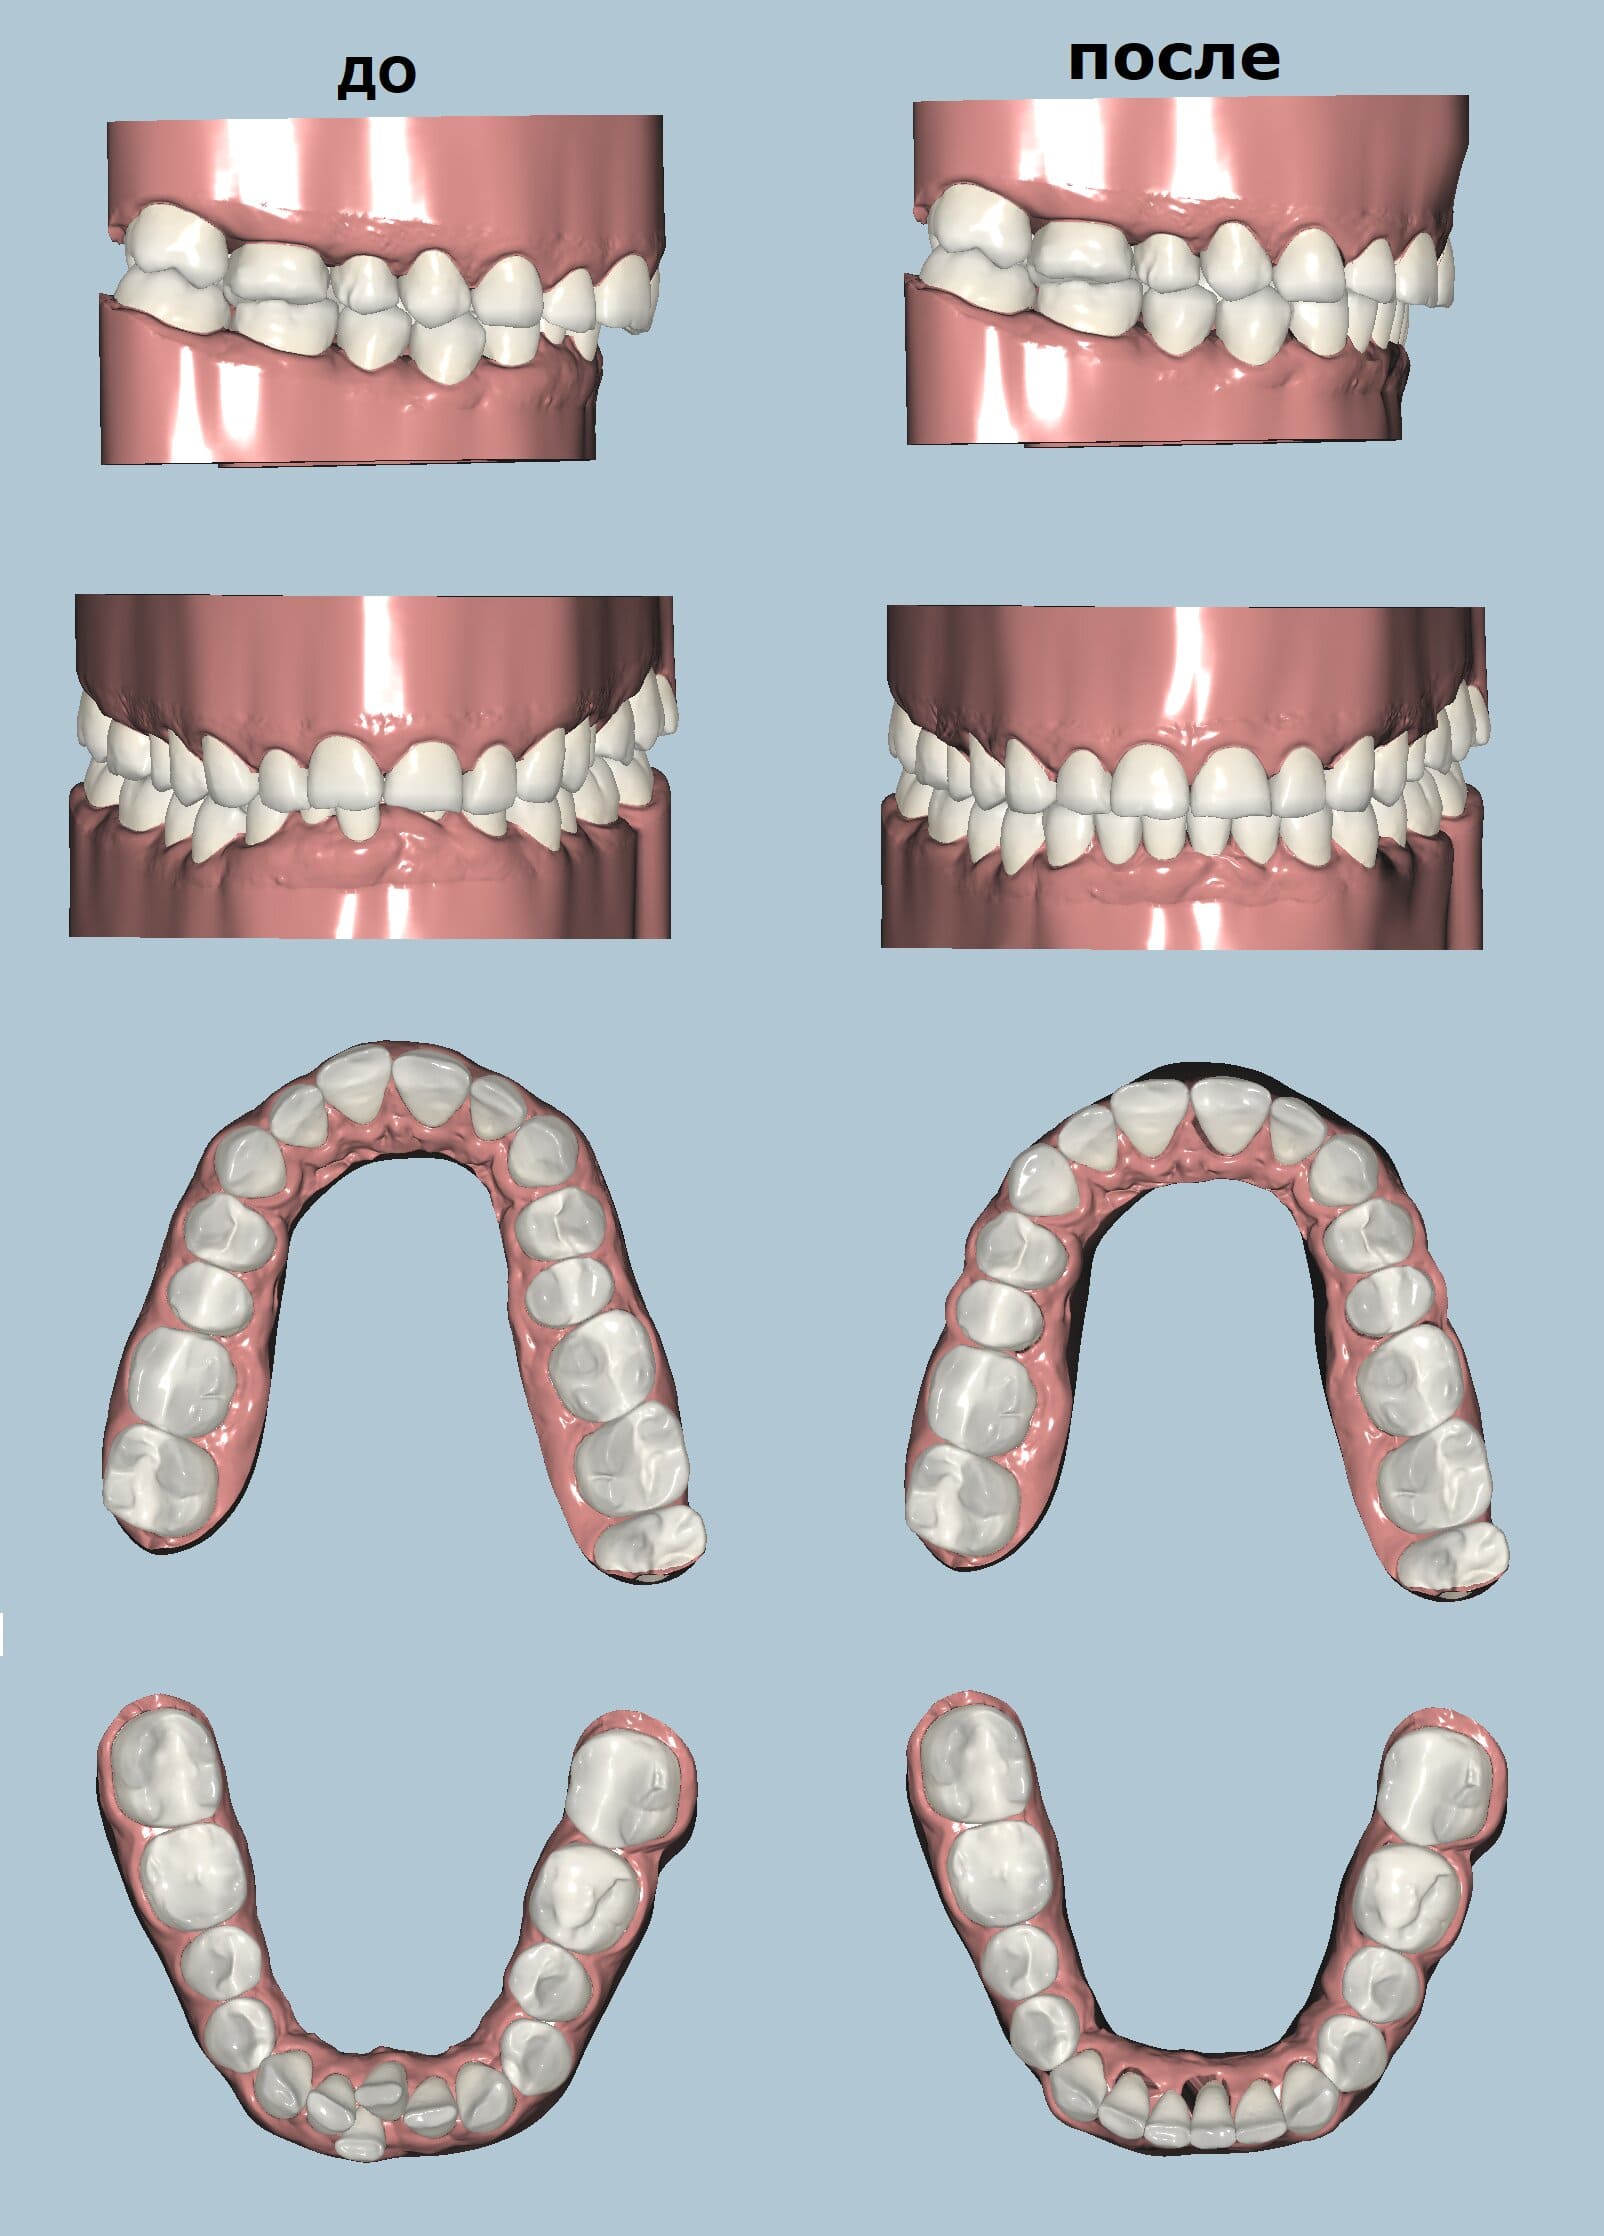

Элайнеры , одно из самых передовых, точных и востребованных решений для лечения неправильного прикуса, используются для выпрямления или корректировки зубов без металлических брекетов, колец и дуг. Элайнеры имеют эстетические и медицинские преимущества по сравнению с обычными металлическими брекетами. Они обеспечивают лучшие результаты, чем традиционные брекеты, по той же цене, часто с меньшим количеством посещений стоматолога и меньшим временем лечения.

Ниже есть выгрузка видео с этапами перемещения зубов. Этот пациент начал лечение в феврале 2023 года. Этапы лечения будем выкладывать.